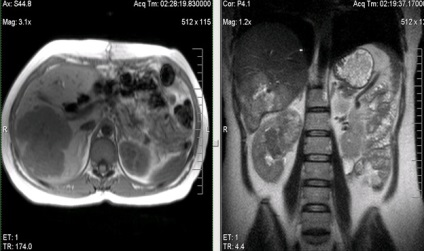

Egyedi kis májáttétek; hasonlóság a natív vizsgálat hemangiomas.

Ugyanez a beteg. Postkontrastnye tomográfia. Egyedi kis májmetasztázisok ellentétben hemangiomas tomogramjait a korai és a késői fázisban válik parenchymás hypointense a natív vizsgálat (gyors enyhülést kontraszt kritérium 1 perc).

Áttétek a májban, a jobb vesét.